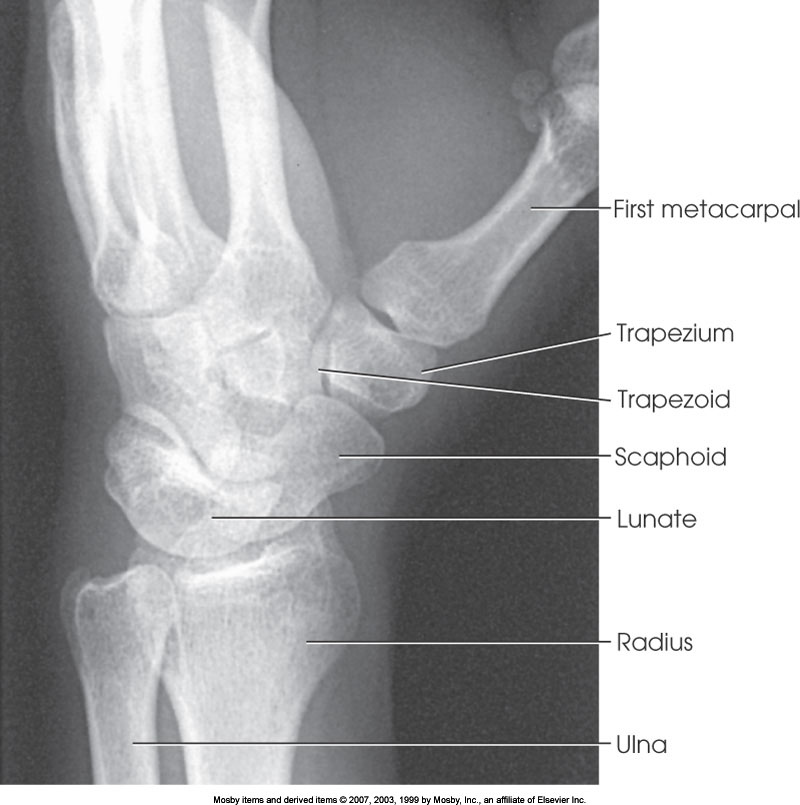

What position is demonstrated?

PA Oblique Wrist